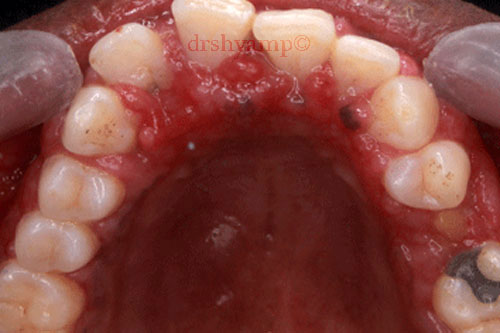

Prgenancy Gingivitis